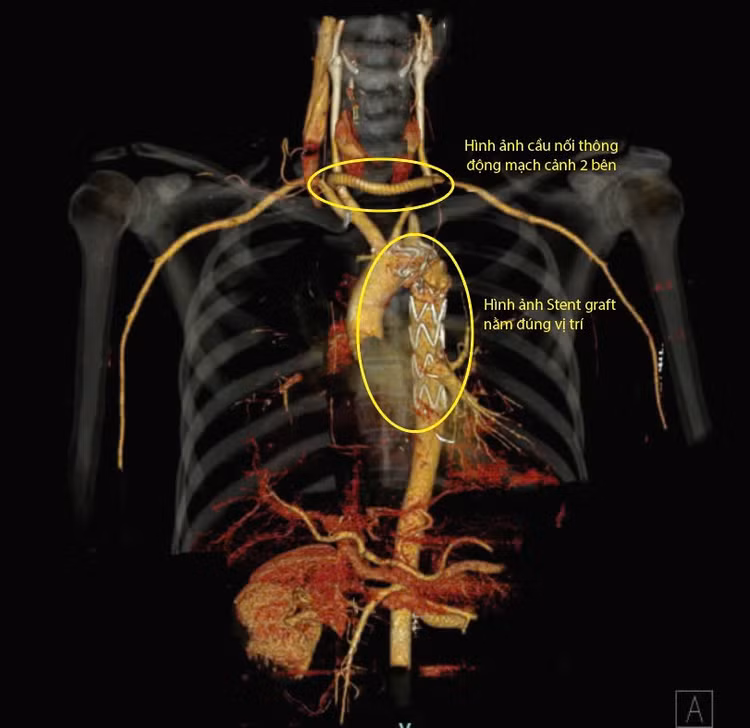

Toàn bộ quá trình phẫu thuật, đến can thiệp chỉ diễn ra trong khoảng 04 tiếng. Người bệnh điều trị hậu phẫu sau 08 ngày đã ổn định, không đau ngực, huyết áp và nhịp tim ổn định. Người bệnh đã được kiểm tra bằng chụp CT 128 dãy, vị trí đặt Stent Graft đúng, tưới máu tạng tốt và không có bất kỳ biến chứng nào có thể ra viện sau vài ngày tới.

| Hình ảnh động mạch chủ ngực sau khi được đặt Stent và hình ảnh cầu nối động mạch cảnh hai bên bằng mạch máu nhân tạo - Ảnh BVCC |